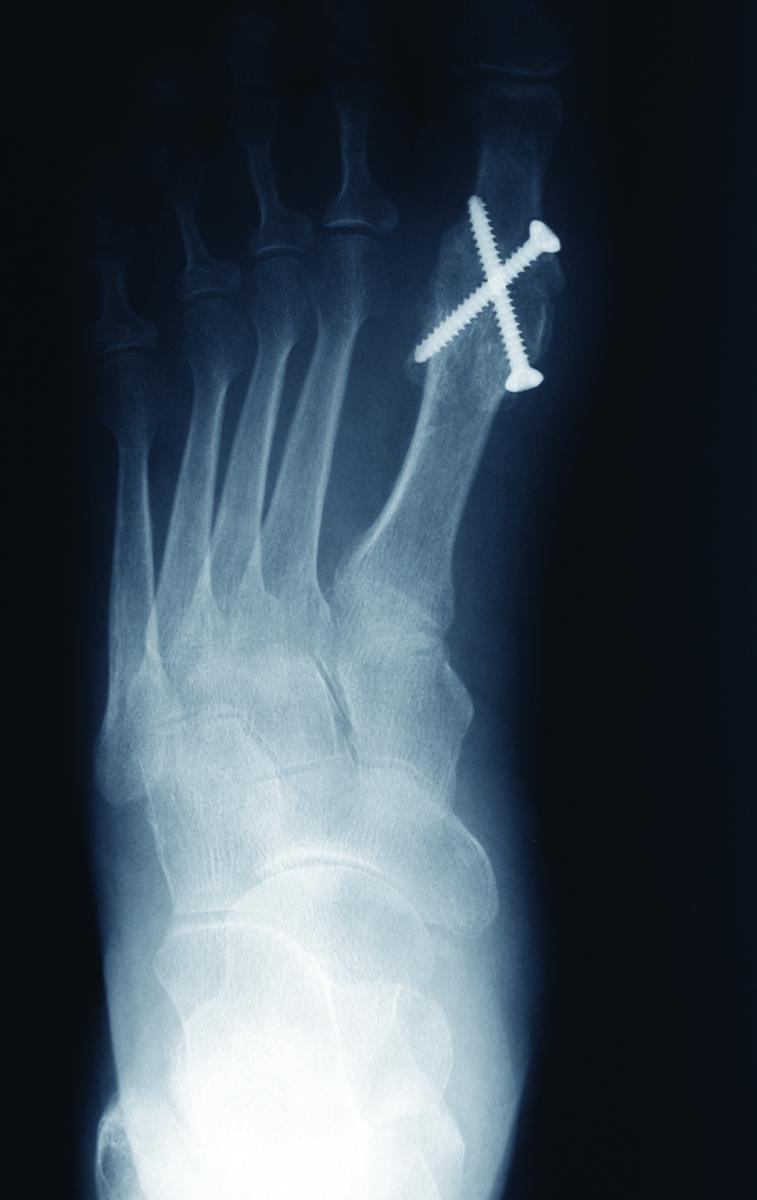

Study: Dual Crossed Screws Effective For First MPJ Arthrodesis

A new study in the Journal of Foot and Ankle Surgery concludes that fixation with dual crossed screws can lead to successful arthrodesis for the first metatarsophalangeal joint (MPJ).

Researchers focused on 262 feet in 228 patients who had first MPJ fusion fixated with dual crossed 3.0 mm screws. The study authors achieved successful arthrodesis in 252 feet and noted that the mean time to radiographic evidence of arthrodesis was seven weeks. Two hundred patients reported little to no pain with 173 reporting that they were able to wear any type of shoe after surgery, according to the study.

Study co-author Peter Blume, DPM, FACFAS, cites several advantages of dual crossed screw fixation over other methods, including that dual crossed screws allow for uniform compression across the first MPJ. He also notes a few pros of using screws without a plate, such as a reduction of surgical time and that patients can typically walk two weeks after surgery in a controlled ankle motion boot due to the rigid fixation of the dual screw method.

Furthermore, fixation with a plate can become a source of skin irritation, necessitating its removal, according to Dr. Blume, an Assistant Clinical Professor of Surgery in the Department of Surgery and an Assistant Clinical Professor of Orthopaedics and Rehabilitation in the Department of Orthopaedics, Section of Podiatric Surgery at the Yale University School of Medicine in New Haven, Ct. He also notes that with dual crossed screws, surgeons place wires across the joint and then advance a cannulated screw over the wire in position and confirm placement with intraoperative fluoroscopic guidance.

As Patrick DeHeer, DPM, FACFAS, notes, crossed screws are less expensive than procedure-specific plates and locking screws, and are more stable and less expensive than staples.

Although the literature shows mixed results, generally, crossed screws are less stable than locking plates with compression screws, notes Dr. DeHeer, a Diplomate of the American Board of Podiatric Surgery, who is in private practice in Indianapolis. Additionally, he says research has shown crossed screws to have higher non-union rates than locking plates with compression screws.

However, Dr. DeHeer adds that crossed screws can be an effective method of fixation for numerous hindfoot and midfoot arthrodesis procedures.

Dual crossed screw fixation is most effective in patients with deformities of the first MPJ with enough bone stock to allow for compression with two screw fixation, maintains Dr. Blume. In addition, he says the two screw fixation can be effective for Lapidus-type procedures, calcaneocuboid joint arthrodesis and midfoot fusions. However, Dr. Blume notes that if the patient has very osteoporotic bone or large bone cysts, a plate would provide a stronger construct than dual crossed screws.